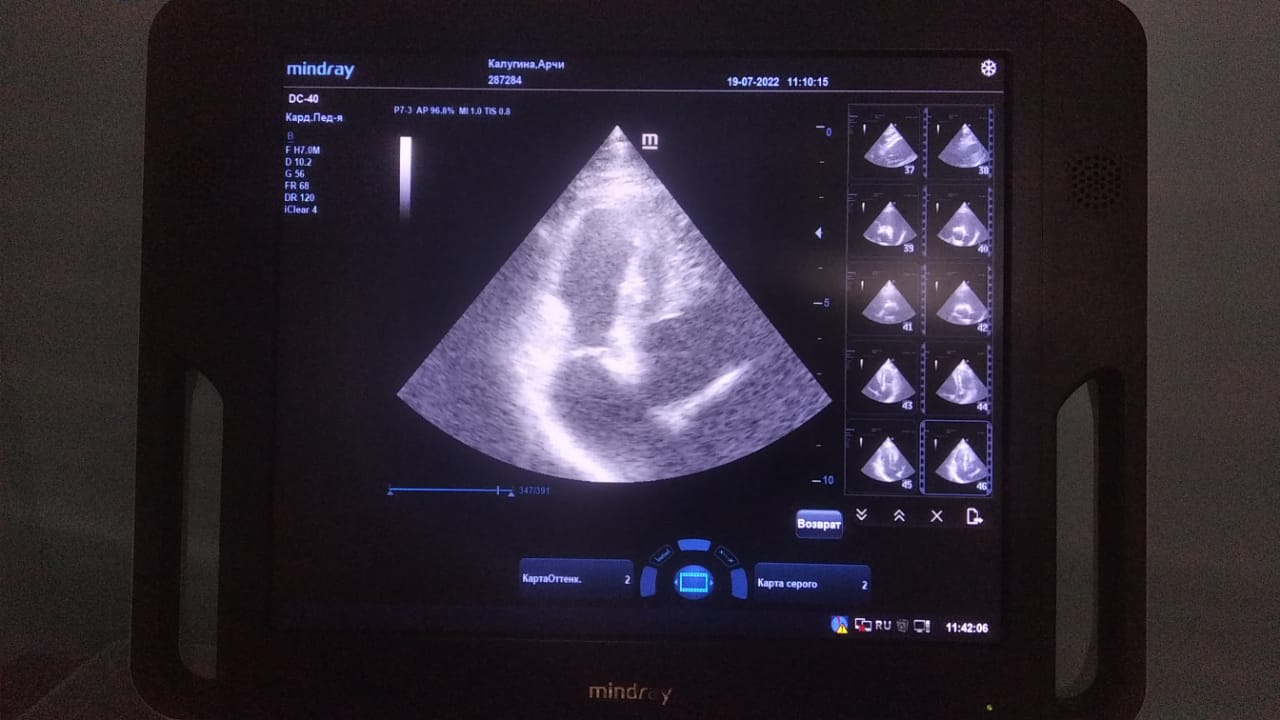

Анализы Арчи. Сердца и легких

Вложения

IMG-20220719-WA0100.jpg

IMG-20220719-WA0102.jpg

IMG-20220719-WA0104.jpg

IMG-20220719-WA0103.jpg

IMG-20220719-WA0105.jpg